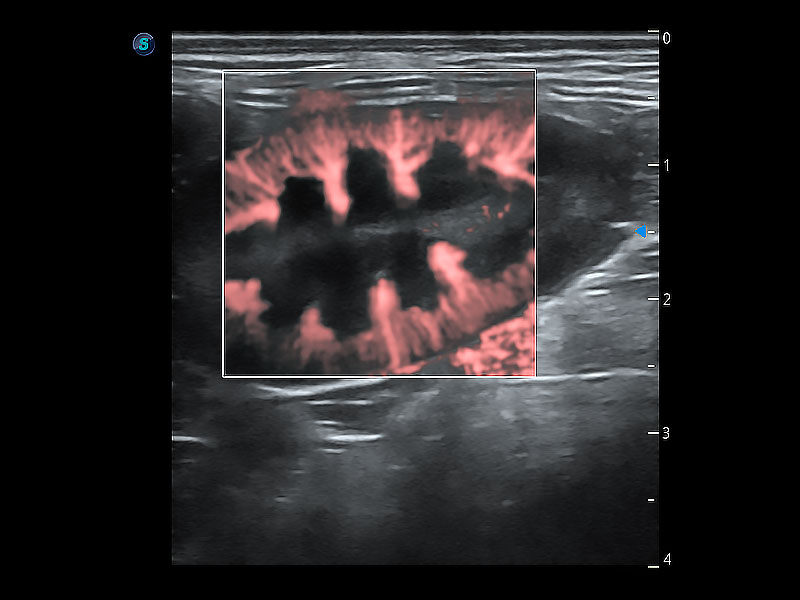

極大提升超低速微細(xì)血流的檢出能力,同時(shí)更精準(zhǔn)地濾除軟組織和超聲信號(hào),為獸用醫(yī)生提供以往無(wú)法通過(guò)常規(guī)血流獲得的疾病診斷信息。

在傳統(tǒng)二維血流成像的基礎(chǔ)上,呈現(xiàn)血流的立體感,具有動(dòng)感的生命力之美。即便是微小的血管也能輕松應(yīng)對(duì),提高了血流的視覺敏感性。